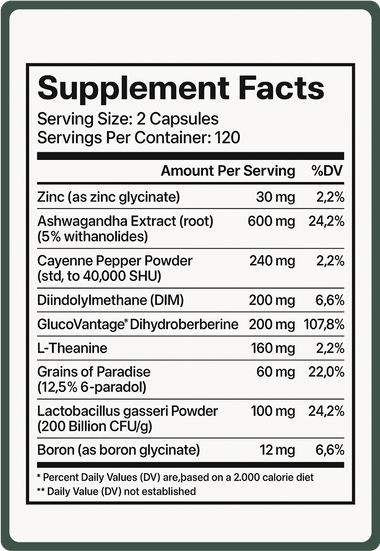

2 Capsules a Day → 9-Clinically Backed Ingredients → 1 Transformation

The #1 Scientifically Formulated Supplement For Men Over 30

What’s Inside Dryft™ ?

Every ingredient in Dryft™ is scientifically-supported to promote natural vitality. No fillers, no unnecessary additives, just 9 powerful compounds that work together to help improve body composition and support the confident man you want to be.